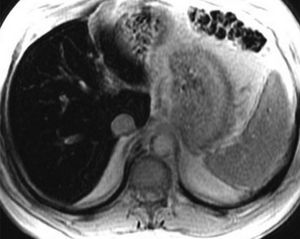

GRE T2*-weighted MR imaging performed in a dedicated study to investigate iron overload. Axial image of a patient with severe iron overload demonstrates accentuated decrease in the liver signal intensity because of the increased R2* (1/T2*) (Queiroz-Andrade et al 2009).